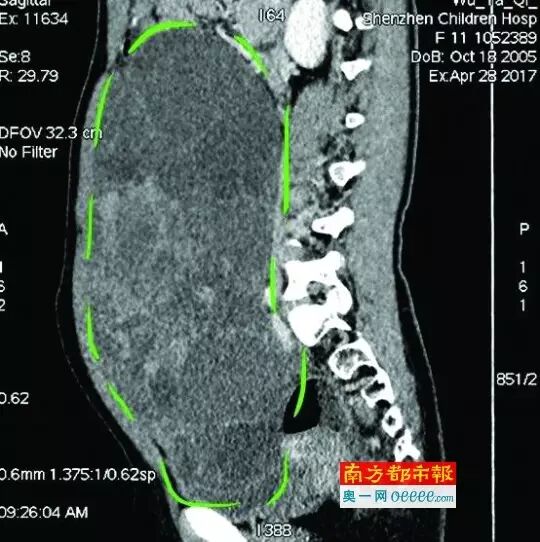

CT检 查图像。

入院后,普外一科肖东主任向家长询问了病史,仔细进行了体格检查,并完善腹部CT。CT结果提示,孩子的大部分腹腔、盆腔被一个巨大的肿瘤占据,肠道、血管和肾盂都受到了不同程度的压迫。从C T上看,肿瘤很可能起源于左侧的卵巢。

手术中发现,小琪腹中的肿瘤体积巨大,大小约为25×20×15厘米,表面光滑,来源于左侧卵巢。医生们首先将其与周围的组织小心剥离,然后将这个占据孩子腹腔、盆腔大部分的巨大包块完整切除,切除肿瘤后还重建了左侧卵巢。剖开瘤体,发现瘤体为囊性及实性混合组成,瘤体内部充盈着粘液状的液体,重量达到了3000克。术后小琪病情稳定,测量腹围从术前的72厘米减小到了62厘米。